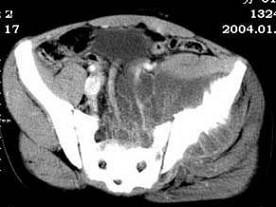

问题 女,35岁,7个月前无诱因出现左下肢阵发性疼痛,左骶髂部活动受限,进行性加重,排便困难,请根据所提供的图像,选择最佳选项 ( )

选项 A、转移瘤 B、滑膜肉瘤 C、软骨肉瘤 D、骨巨细胞瘤 E、脊索瘤

答案 B